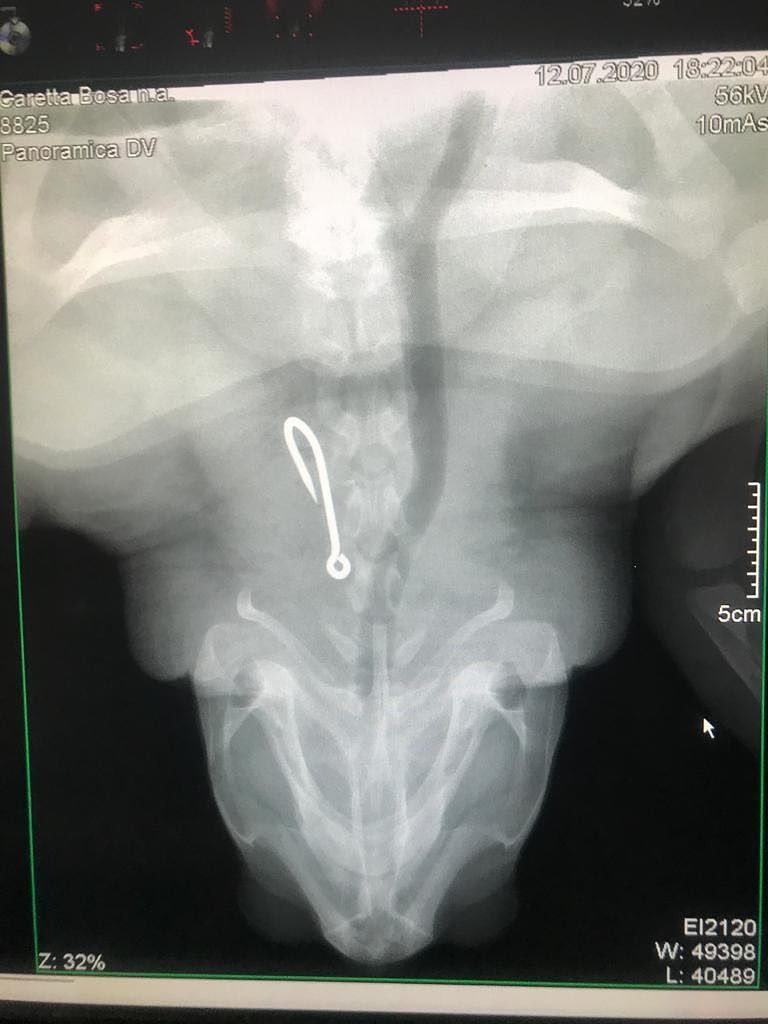

“Dalla radiografia – racconta Andrea Camedda, ricercatore del Cres – è emersa la presenza di un grosso amo da palamito a livello dell’esofago, che sarà rimosso dai veterinari. Dopo l’intervento chirurgico la tartaruga trascorrerà la degenza in una vasca al CReS a San Giovanni di Sinis e sarà seguita dai biologi del CNR e dell’AMP del Sinis per tutto il periodo di riabilitazione e monitoraggio prima del suo rilascio in natura”.

“Dalla radiografia – racconta Andrea Camedda, ricercatore del Cres – è emersa la presenza di un grosso amo da palamito a livello dell’esofago, che sarà rimosso dai veterinari. Dopo l’intervento chirurgico la tartaruga trascorrerà la degenza in una vasca al CReS a San Giovanni di Sinis e sarà seguita dai biologi del CNR e dell’AMP del Sinis per tutto il periodo di riabilitazione e monitoraggio prima del suo rilascio in natura”.